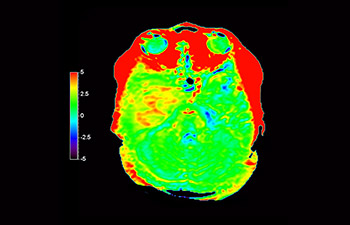

Astrocytoma

Brain astrocytoma, post-radiotherapy

with 3D APT

3D APT (Amide Proton Transfer) is a unique, contrast-free, brain MR imaging method addressing the need for more confident diagnosis in neuro oncology. 3D APT uses the presence of endogenous cellular proteins, to produce an MR signal that directly correlates with cell proliferation, a marker of tumoral activity. 3D APT can support trained medical professionals in differentiating low grade from high grade gliomas and, in differentiating tumor progression from treatment effect1.